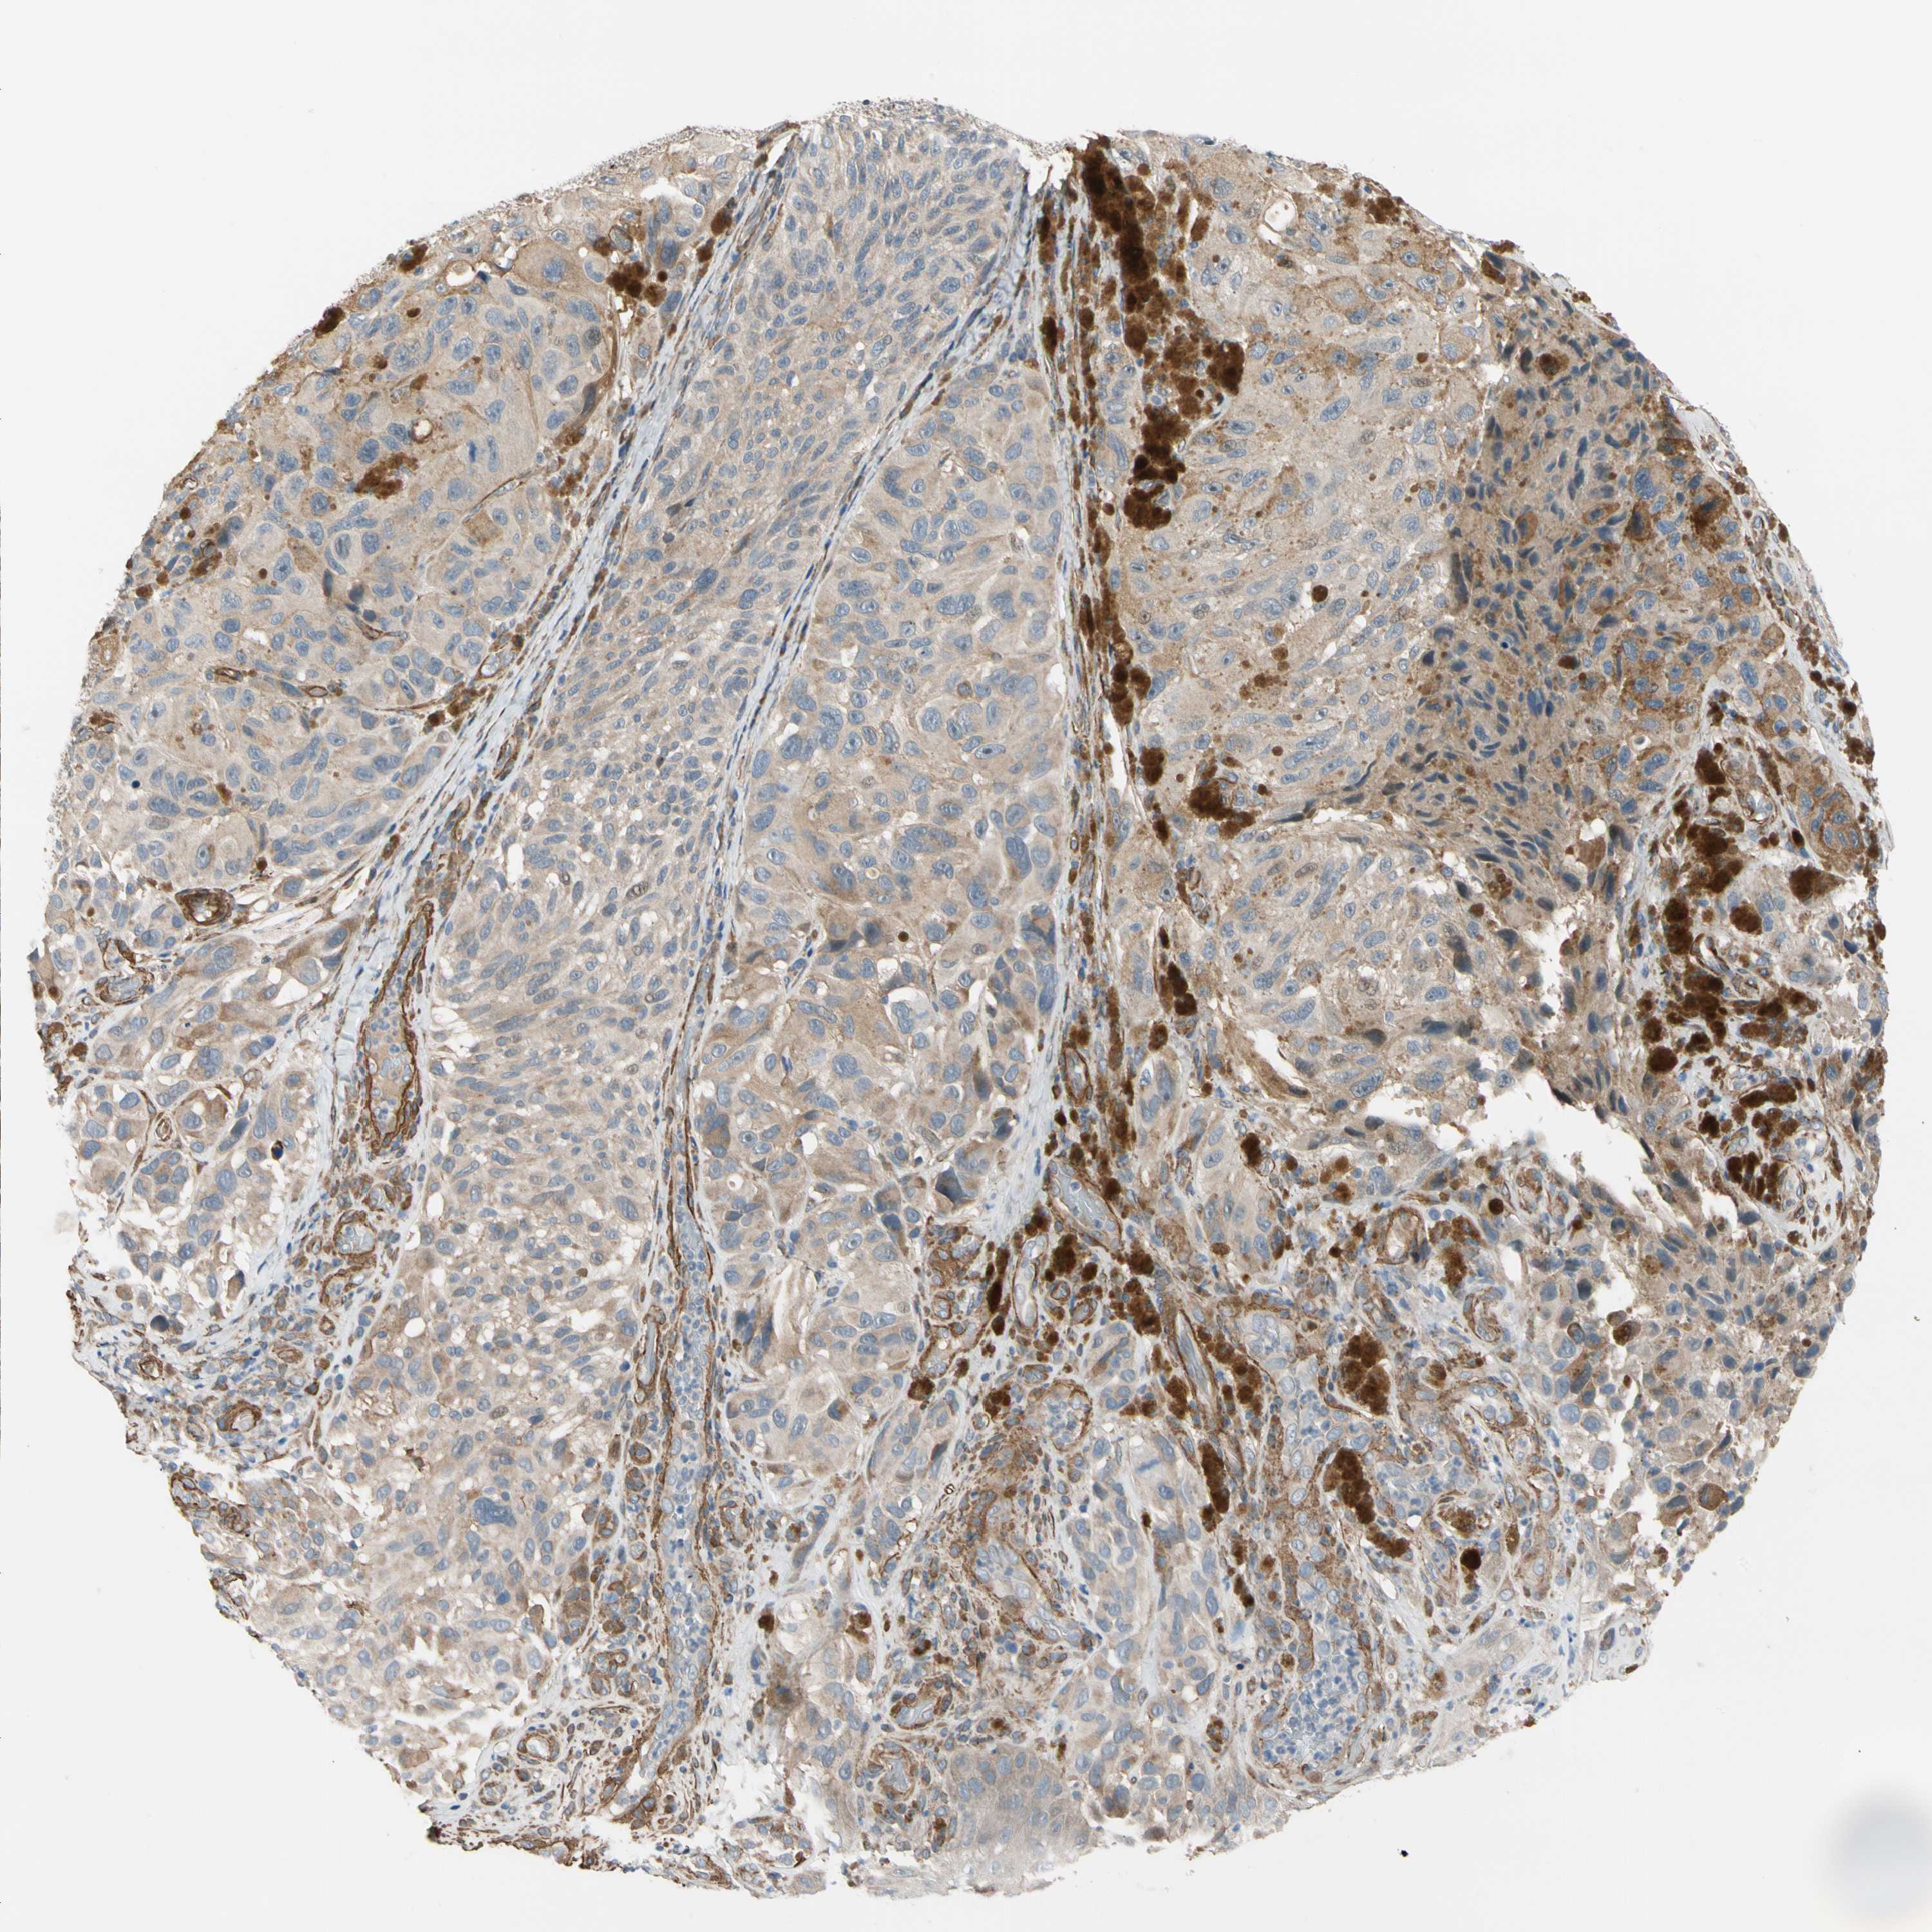

MELANOMA - Protein expressioni

A mouse-over function shows sample information and annotation data. Click on an image to view it in a full screen mode. Samples can be filtered based on level of antibody staining by selecting one or several of the following categories: high, medium, low and not detected. The assay and annotation is described here.

Note that samples used for immunohistochemistry by the Human Protein Atlas do not correspond to samples in the TCGA dataset.

Antibody stainingi

Antibody staining in the annotated cell types in the current human tissue is reported as not detected, low, medium, or high, based on conventional immunohistochemistry profiling in selected tissues. This score is based on the combination of the staining intensity and fraction of stained cells.

Each image is clickable and will lead to virtual microscopy that enables deeper exploration of all samples and also displays staining intensity scores, fraction scores and subcellular localization as well as patient and tissue information for each sample.

Antibody HPA008183

Antibody HPA053882

Antibody CAB019313

Staining

High

Medium

Low

Not detected

Intensity

Strong

Moderate

Weak

Negative

Quantity

>75%

75%-25%

<25%

None

Location

Nuclear

Cytoplasmic/membranous

Cytoplasmic/membranous,nuclear

Malignant melanoma, NOS

Malignant melanoma, Metastatic site